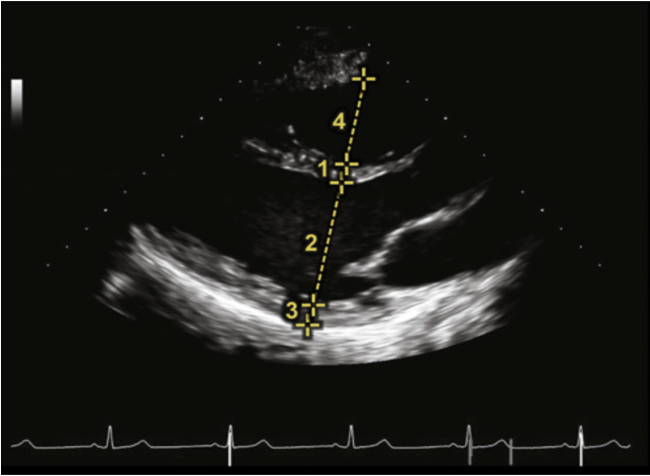

(4)左室短轴切面面积变化分数(LV-FAC%):在胸骨旁短轴(PSAX)乳头肌切面(图24),清晰显示心内膜以后,分别勾勒左室舒张末面积(LVEDA)和左室收缩末面积(LVESA),通过下面公式进行计算:

LV-FAC%=(LVEDA-LVESA)/LVEDA×100%

LVFAC%的参考值为50%~75%。

图片

图24. PSAX乳头肌切面测量LVEA